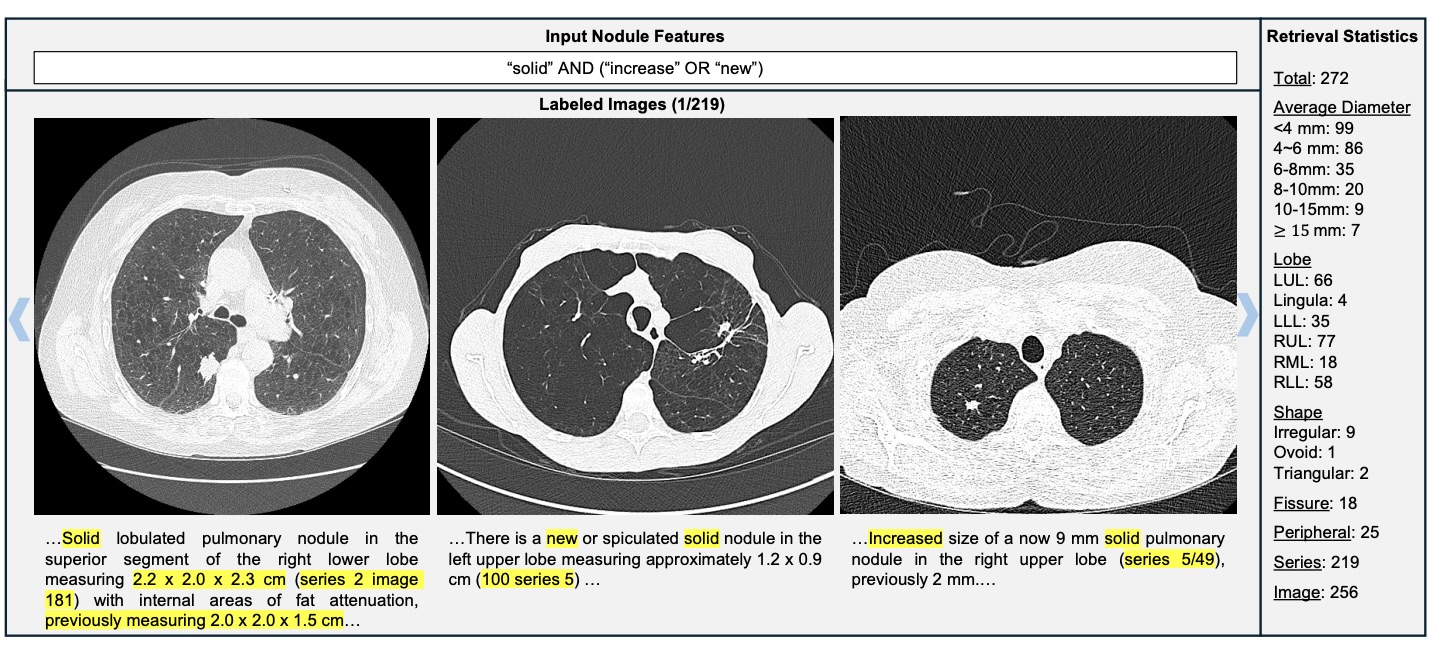

Figure 8: Complex semantic query: solid AND (increase OR new) → 272 nodules retrieved.

Unlike keyword matching, semantic reasoning detects growth even when "increase" is not explicitly mentioned.